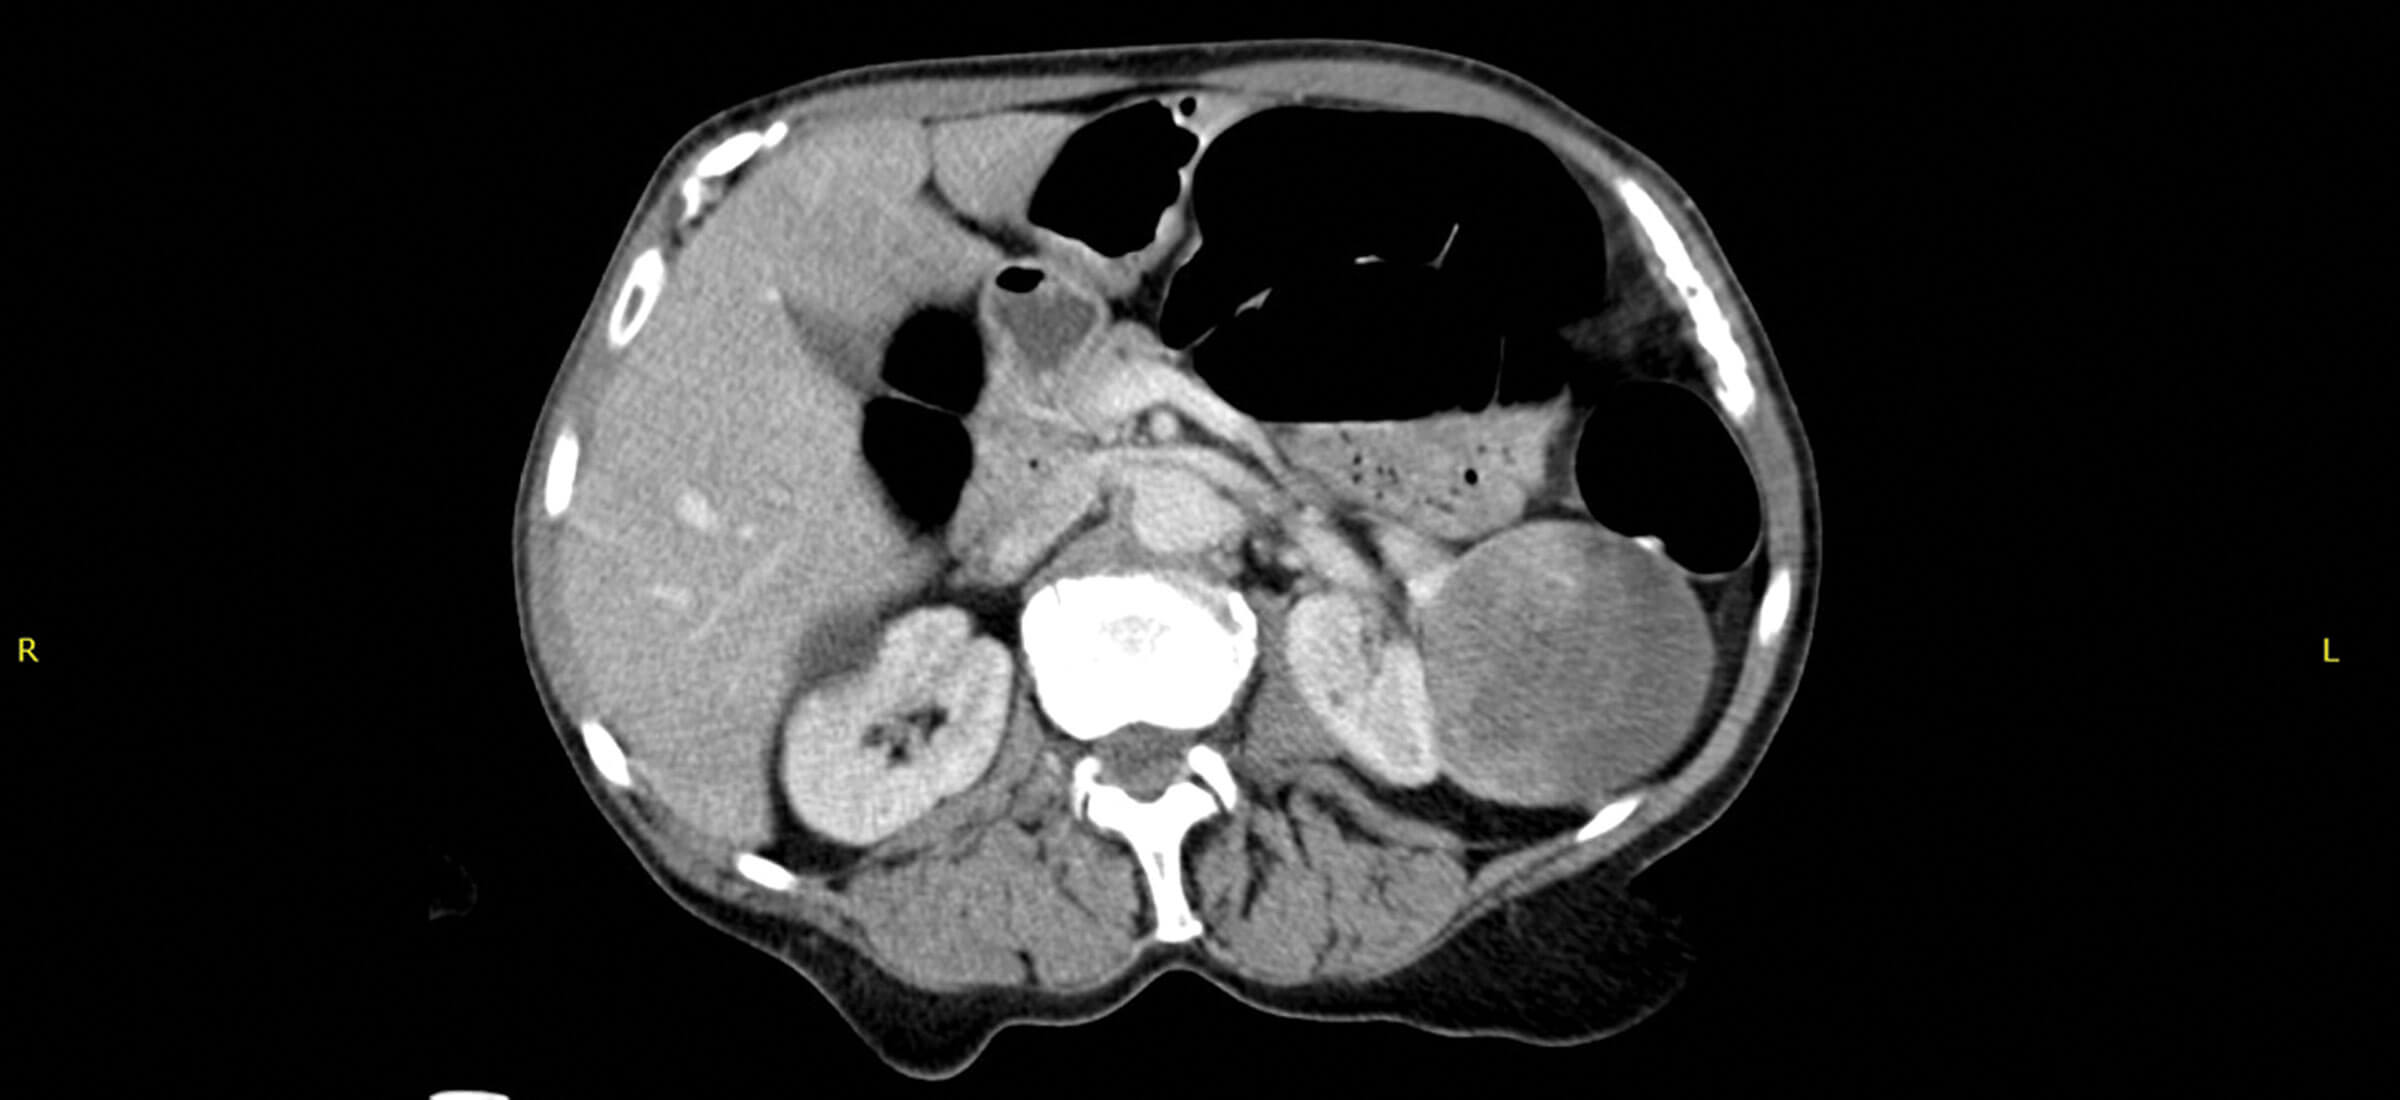

A 70-year-old female presented under the medical team with malaise, weight loss, and deranged liver function tests (LFTs) and calcium (ALP 350, GGT 650, Serum bilirubin 29, normal aminotransferases, Ca 3.3). An abdominal ultrasound scan (USS) was performed which demonstrated hepatosplenomegaly and an incidental finding in the kidney. A CT was arranged (Figure 1).

Figure 1.

What does the CT in Figure 1 show?

1. A large cystic mass within the left kidney.